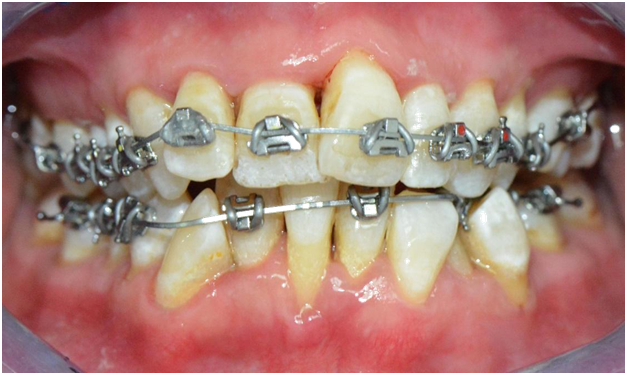

The patient received scaling and root planing followed by the application of brackets on the four maxillary anterior teeth for patient comfort (Figures 4). A subsequent appointment specifically addresses the application of brackets on the lingually inclined teeth while avoiding bracket application on labially inclined teeth (Figure 5). As the roots of previously lingually inclined teeth upright, brackets are placed on all teeth at a subsequent appointment (Figure 6). Clinical results along with photographs comparing pre and post treatment show dramatic periodontal and esthetic improvement, particularly with alveolar bone development and the reversal of recession (Figure 7). Treatment results are impressive as uprighting of the malpositioned roots creates remodeling of alveolar bone to accommodate the boney support of the properly aligned tooth. Post-treatment results also show a stable occlusion with proper overjet and overbite relations.

Figure 4 After scaling of teeth and application of four brackets on the maxillary anterior teeth for patient comfort, (Courtesy of Dr. Patrick Assal, Lausanne Switzerland).